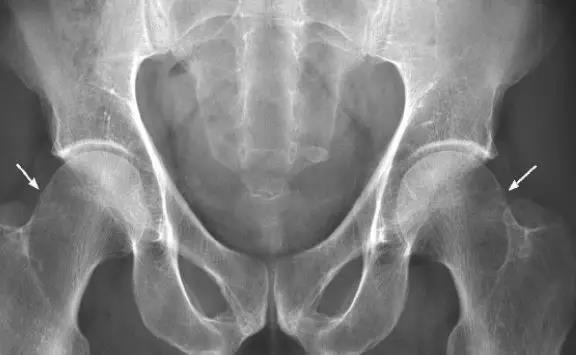

- 正常髋关节X线表现。

- 中心边缘角(LCE角)正常范围为25一39;髋臼指数(AI)正常值>0;挤压指数(E/A+E)正常值<25%。

- IIL:髂坐线;AW:髋臼前壁缘;PW:髋臼后壁缘;A为股骨头被髋臼覆盖部分的宽度;E为股骨头未被髋臼覆盖部分的宽度;F为髋臼窝线。